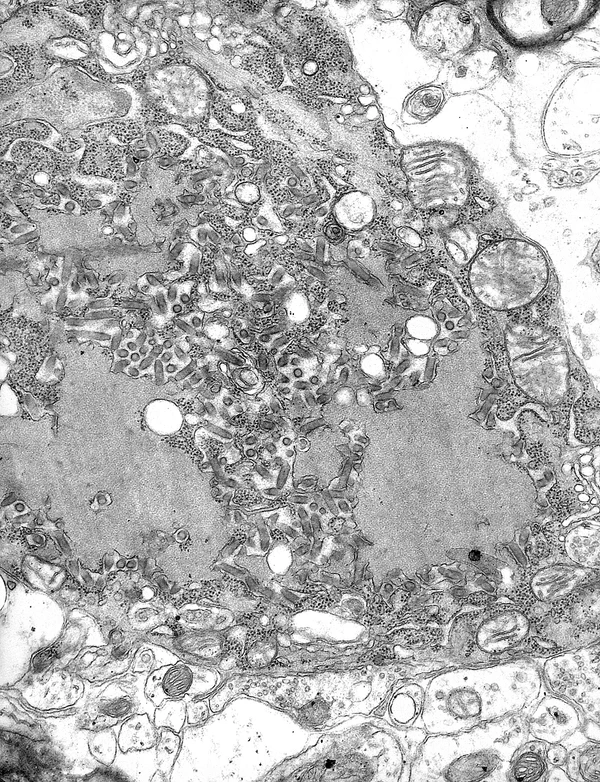

Все события транскрипции и репликации происходят в цитоплазме внутри телец Бабеша — Негри (названных в честь Виктора Бабеша и Адельки Негри[8]). Диаметр их составляет 2—10 мкм; они являются типичными при бешенстве и, таким образом, могут быть использованы в качестве патогномоничного симптома наличия инфекции[9].